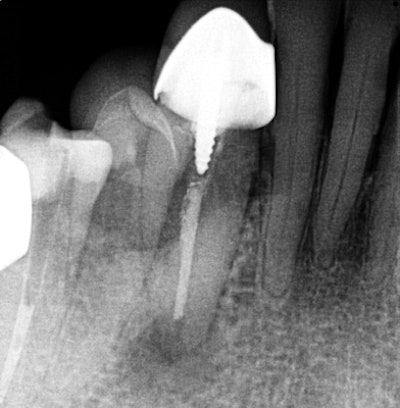

The second case is of a 70-year-old patient of record who called early on a Monday morning and stated that he was up all night in severe pain. His chief complaint was pain in the lower right quadrant. On examination, I determined that his swelling spanned from the lower right lateral incisor to the second premolar, with concomitant pain to palpation and percussion. A Schick 33 (Sirona) periapical radiograph was taken, revealing the lower right canine as the culprit.

A previously treated endodontic tooth was failing. On initial review, I considered dismantling and retreating. The fill appeared to be short of the apex, but because of the extent of the swelling and level of pain, I wanted to evaluate in an enhanced 3D scan. The imaging led to my referral of this patient to an oral surgeon for an apicoectomy in an effort to retain this tooth.

Interestingly, the tangential view was similar to the periapical view, but the cross-sectional view influenced my decision.

Looking carefully, one can see that the fill was well-done, and the buccal lingual tooth length was not the same in the horizontal plane. I did not feel that retreatment could improve this situation. An extraction and bone graft would not be the first choice, as his dentition was extremely crowded in this area. Crown and bridge also would be challenging to say the least.